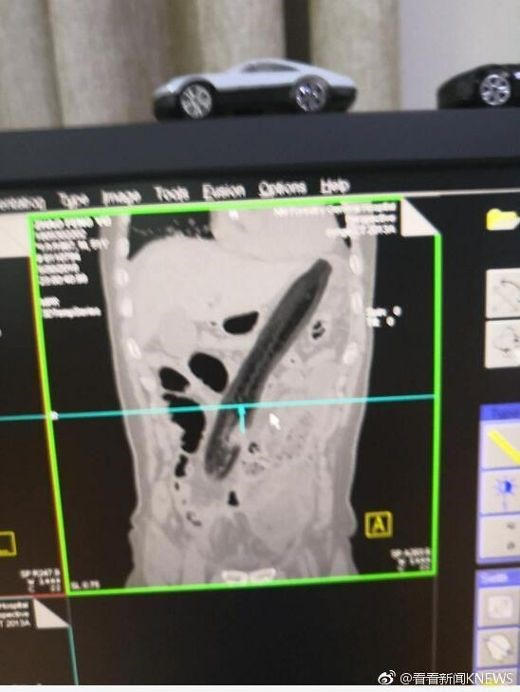

Kinh sợ người đàn ông nhét quả cà tím dài 30cm vào hậu môn để chữa táo bón

Sau khi bị đau bụng và táo bón trong 2 ngày, một người đàn ông Trung Quốc đã quyết định nhét một quả cà tím khổng lồ vào hậu môn.

Tuy nhiên, loại quả này không hề có tác dụng trong việc giải quyết vấn đề của người đàn ông 50 tuổi mà chỉ khiến ông ta cảm thấy đau và khó chịu hơn.

Thậm chí, ông ấy còn có cảm giác buồn nôn.Theo Shanghaiist, cuối cùng, không thể chịu đựng, ông ta đã đến bệnh viện.Kết quả chụp X-quang cho thấy quả cà tím quá lớn và bị đẩy lên tận phía trên làm tổn thương phổi của ông ấy.Bác sỹ đã rút "vật thể lạ" ra ngoài và đo được nó dài khoảng 30cm.